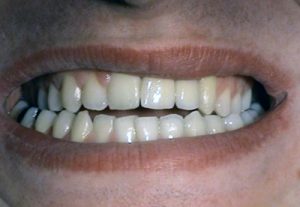

3. PHASE – prosthetic fabrication of temporary crown on implant

3. PHASE – fabrication of temporary solution